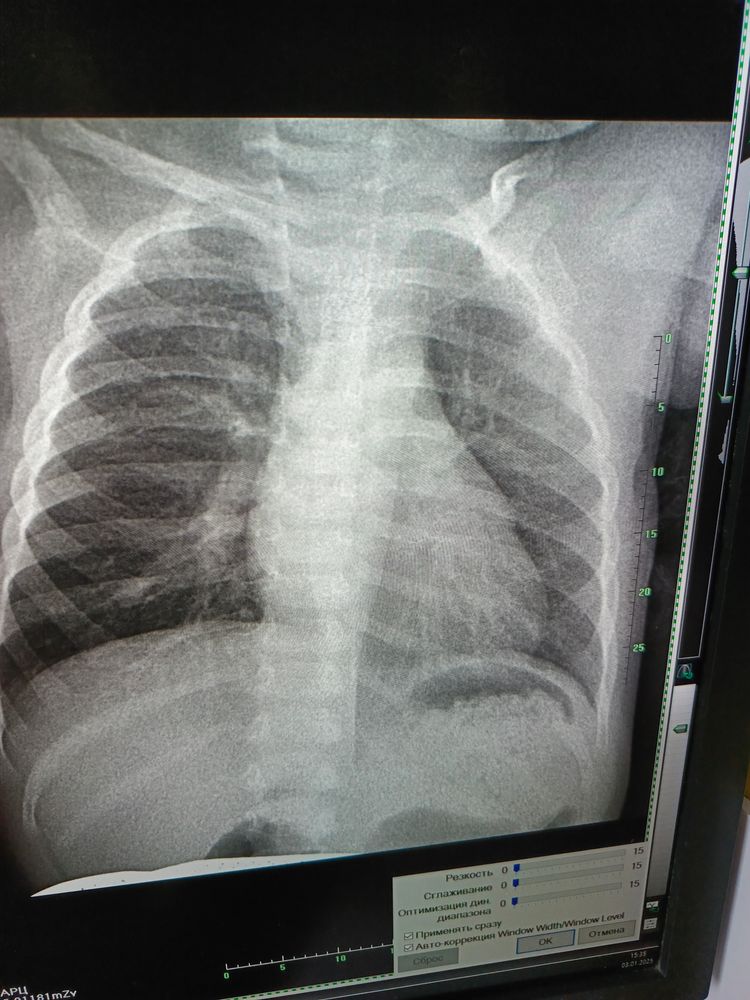

Девочки, добрый вечер, может кто разбирается в снимках? Дочке 1.5 , у нас мокрый кашель, сопли, расшифровка будет готова через несколько дней, я сфотографировала, может кто понимает?! Говорят пневмония или бронхит острый, температуры у нас нет